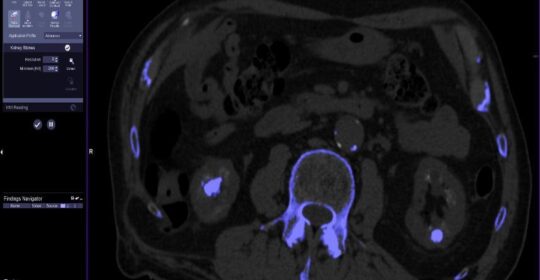

Otro de los grandes avances es el papel que juega la imagen en el diagnóstico de patologías cada vez más complejas. La combinación de tecnologías como la resonancia magnética, la tomografía computarizada multicorte (TAC) o la ecografía de alta resolución permite obtener una visión completa y detallada de órganos, tejidos y estructuras internas sin necesidad de procedimientos invasivos.

Además, los equipos actuales cuentan con software avanzado de reconstrucción 3D, inteligencia artificial y herramientas de cuantificación que proporcionan una gran cantidad de información objetiva y reproducible. Esto no solo ayuda al especialista en radiología a identificar alteraciones sutiles, sino que permite establecer diagnósticos más personalizados y ajustados a la realidad clínica de cada paciente.

La radiología intervencionista ha abierto la puerta a tratamientos mínimamente invasivos guiados por imagen, que permiten actuar directamente sobre la lesión con la máxima precisión y un menor impacto para el paciente. Técnicas como las biopsias dirigidas por ecografía o TAC, la radiofrecuencia, la embolización o la vertebroplastia, son ejemplos claros de cómo la imagen no solo diagnostica, sino que también cura.

Además, la imagen permite monitorizar en tiempo real la evolución del tratamiento, ajustarlo si es necesario y valorar la respuesta de forma objetiva. Esto resulta especialmente útil en terapias oncológicas, musculoesqueléticas, hepáticas o urológicas.